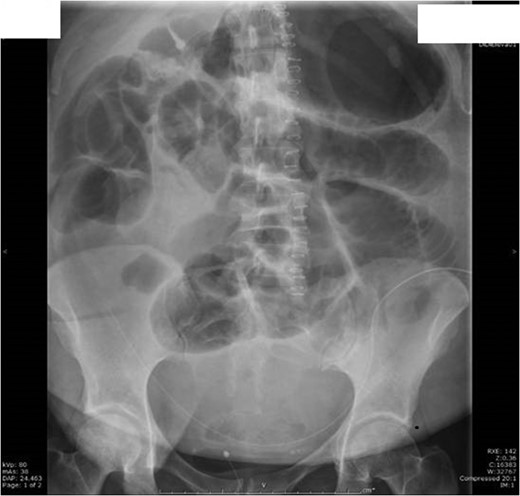

The next day she had fever with rigors, night sweats, ongoing abdominal pain and distension. Her bowel sounds were reduced and she had stopped passing flatus. She was treated for sepsis with likely respiratory source and commenced on intravenous antibiotics. On Day 4 post op she woke up with severe right shoulder tip and right upper quadrant pain radiating to her back. Her chest X-ray showed evidence of pneumoperitoneum (Fig. 3).

Day 4 post op chest X-ray showed a large volume of free gas under both hemi-diaphragms with multiple abnormally dilated loops of large and small bowel-features consistent with perforation of a hollow viscus.